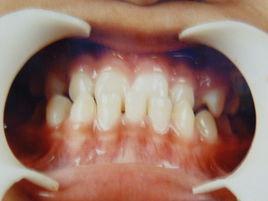

牙齒反合牙齒反合是對牙齒的上下不齊的一種稱謂。通俗的方式講,就是牙齒不齊,也就是平時常說的“地包天”。也被人們稱為"兜齒“,通常表現為下牙包住上牙,不但對咀嚼功能有影響,而且也會因為下巴突出而影響口型的整體美觀。

牙齒反合主要發生在乳牙期或恆牙期,有個別牙反合,也有多數後牙反合。可發生在單側,也可發生在雙側。